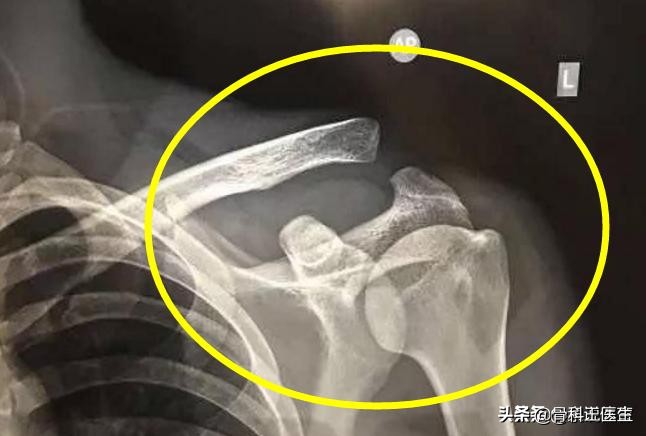

好了,废话不说,如上图,英雄武磊得的是左肩锁关节脱位!

4、我们再来看看武磊的X线:是个三度的脱位,也就是最严重的肩锁关节脱位!